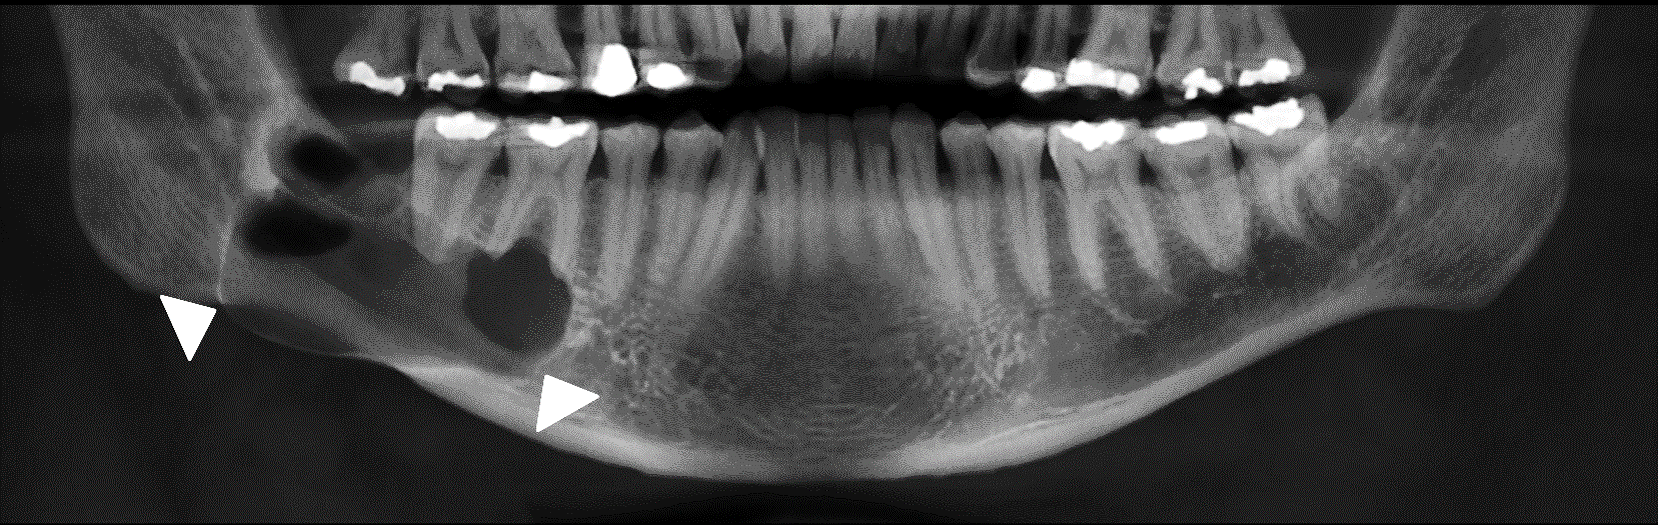

Different types of radiographic features seen in ameloblastoma Download Scientific Diagram Ameloblastoma Incidence This accounts for more or less 1% of tumors. They constitute 1% of tumors and. About 80% of ameloblastomas occur in the mandible mainly the third molar region and the remaining 20% in the upper jaw. The estimation of annual incidence of ameloblastoma is 0.5 per million population. Ameloblastoma is a rare head and neck tumor with an estimated annual. Ameloblastoma Incidence.

Ameloblastoma Radiology Cases Ameloblastoma Incidence They constitute 1% of tumors and. The estimation of annual incidence of ameloblastoma is 0.5 per million population. They also found that malignant ameloblastoma, comprising. Ameloblastoma is a rare head and neck tumor with an estimated annual incidence of 0.5 per million population [citation 1, citation 2]. The rate of incidence was higher in males than females and also higher. Ameloblastoma Incidence.

Ameloblastoma Radiology Dental Radiology Notes Ameloblastoma Incidence The estimation of annual incidence of ameloblastoma is 0.5 per million population. They constitute 1% of tumors and. This accounts for more or less 1% of tumors. Ameloblastoma is a rare head and neck tumor with an estimated annual incidence of 0.5 per million population [citation 1, citation 2]. The rate of incidence was higher in males than females and. Ameloblastoma Incidence.

Ameloblastoma of the mandible analysis of radiographic and histopathological features Journal Ameloblastoma Incidence About 80% of ameloblastomas occur in the mandible mainly the third molar region and the remaining 20% in the upper jaw. This accounts for more or less 1% of tumors. The rate of incidence was higher in males than females and also higher in the black versus white population. They constitute 1% of tumors and. Ameloblastoma is a rare head. Ameloblastoma Incidence.